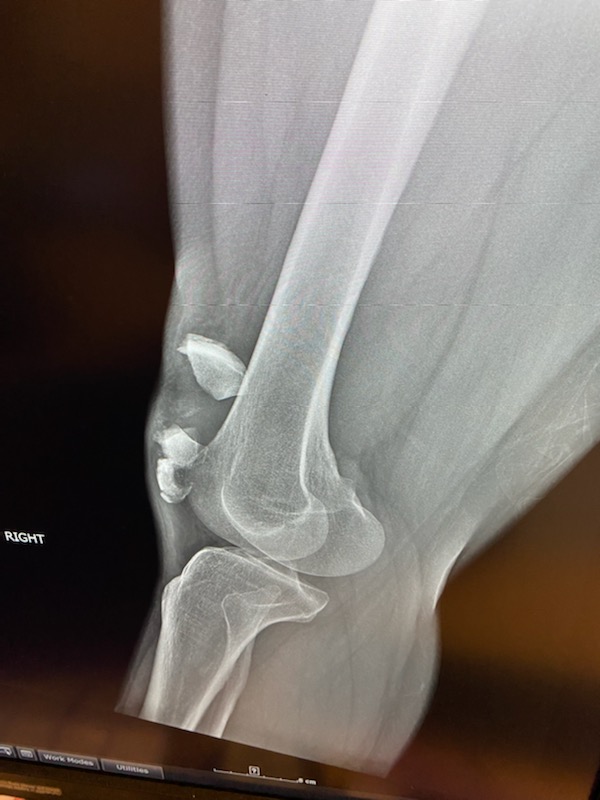

I slipped and fell, fracturing my patella into multiple pieces. I was placed into an immobilizer and sent home to find an orthopedic trauma surgeon. My aunt who is in the orthopedic industry, a friend who is a physical therapist/trainer and another orthopedic physician all highly recommended Dr. Nicholas Sama. Dr. Sama had me in his office literally the next day. He reviewed my records and imaging and explained my injury which was severe. He explained the possible treatments available and the all the risks associated. ORIF of the patella was to be my treatment. I was scheduled the following week at HSS Florida in West Palm Beach, which by the way is a fantastic facility. The procedure was again explained in detail and surgery commenced. Dr. Sama and his team worked meticulously at repairing my patella. Eleven screws and a mesh plate later, surgery was complete. I was placed in an immobilizer and was literally on my feet an hour after surgery. Two months post-op and I'm at 90% full mobility and all done without physical therapy! Dr. Sama literally is a godsend. He is an a amazing surgeon with fantastic bedside manner, which are attributes in the healthcare industry that are hard to find together!